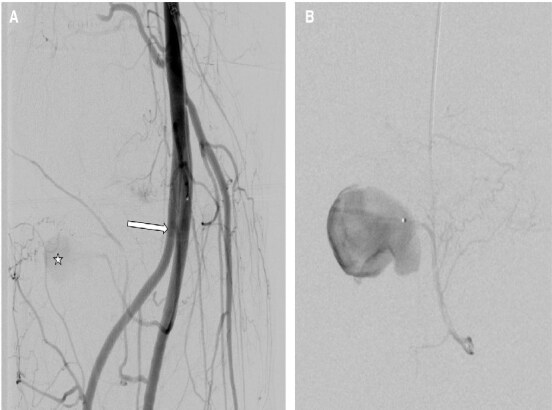

前交叉韧带(ACL)断裂是一种常见的膝关节损伤,通过关节镜重建因其安全性和低并发症发生率(约1%)而广受欢迎。这种手术造成的血管损伤极为罕见,发生率为0.003%-1%。膝关节镜检查后的假性动脉瘤更不常见。本文讨论一例罕见的假性动脉瘤重建后,在右膝内侧间动脉(IMGA)的关节分支,起源于胫骨前动脉高起点。一名47岁的血管性血友病患者在acl重建后30天出现了24毫米的假性动脉瘤。ct血管造影显示假性动脉瘤靠近胫骨隧道螺钉和异常高的胫骨前动脉起源。急诊血管造影证实了这一点,使用Squid Peri 18栓塞成功,无并发症。病人恢复得很好。血管损伤是一种罕见的膝关节镜并发症,但早期诊断和解剖变异的认识是必不可少的。医源性假性动脉瘤的血管内治疗安全有效,且恢复迅速。

Rupture of the anterior cruciate ligament (ACL) is a common knee injury, and reconstruction via arthroscopy is popular for its safety and low complication rate, around 1%. Vascular injuries from this procedure are extremely rare, with an incidence of 0.003%-1%. Pseudoaneurysms following knee arthroscopy are even less frequent. This paper discusses a rare case of pseudoaneurysm after ACL reconstruction in the articular branch of the right inferomedial genicular artery (IMGA), originating from an anterior tibial artery with a high origin. A 47-year-old man with Von Willebrand disease developed a 24 mm pseudoaneurysm 30 days post-ACL reconstruction. CT-angiography showed the pseudoaneurysm near the tibial tunnel screw and an unusually high anterior tibial artery origin. Emergency angiography confirmed this, and embolization using Squid Peri 18 was successful, with no complications. The patient recovered well. Vascular injury is a rare knee arthroscopy complication, but early diagnosis and awareness of anatomical variations are essential. Endovascular treatment for iatrogenic pseudoaneurysms is safe and effective and facilitates rapid recovery.